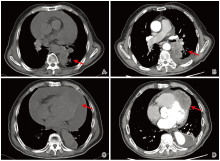

2021-10-09 13∶ 00行超声心动图, 见左右室壁心尖处可见不规则中等偏低回声浸润, 范围约6.5 cm× 3.1 cm, 与原心肌组织分界不清。左右室心尖部异常回声(占位可能); 主动脉瓣轻度返流; 大量心包积液; 室间隔、前壁、侧壁基底段至心尖部应变绝对值降低, 见图3。2021-10-09 14∶ 52行胸部平扫及增强CT显示:左下肺病变伴周围渗出, 大小约6.7 cm× 4.3 cm, 增强不均匀明显强化, 周围局部支气管狭窄闭塞, 考虑肿瘤性病变伴阻塞性肺炎可能并左下肺亚段型不张; 心包积液, 心尖部模糊, 增强见斑片状软组织占位, 考虑转移可能, 见图4。